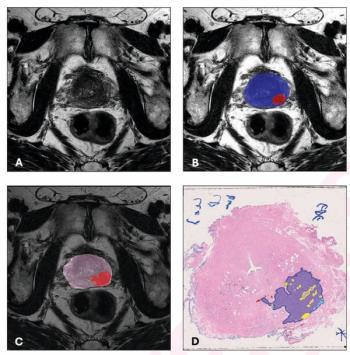

A deep learning multimodal model that incorporates MRI features offered nearly double the sensitivity for predicting post-prostatectomy biochemical recurrence of prostate cancer in comparison to the traditional CAPRA-S scoring system.

Offering an 87 percent sensitivity for clinically significant prostate cancer (csPCa), the deep learning model demonstrated an 86 percent AUC for predicting > PI-RADS 3 lesions on prostate MRI.

The use of adjunctive bpMRI-based AI led to 10 percent and greater increases in lesion-level PPV for csPCa and PCa with a threshold of PI-RADS > 3.